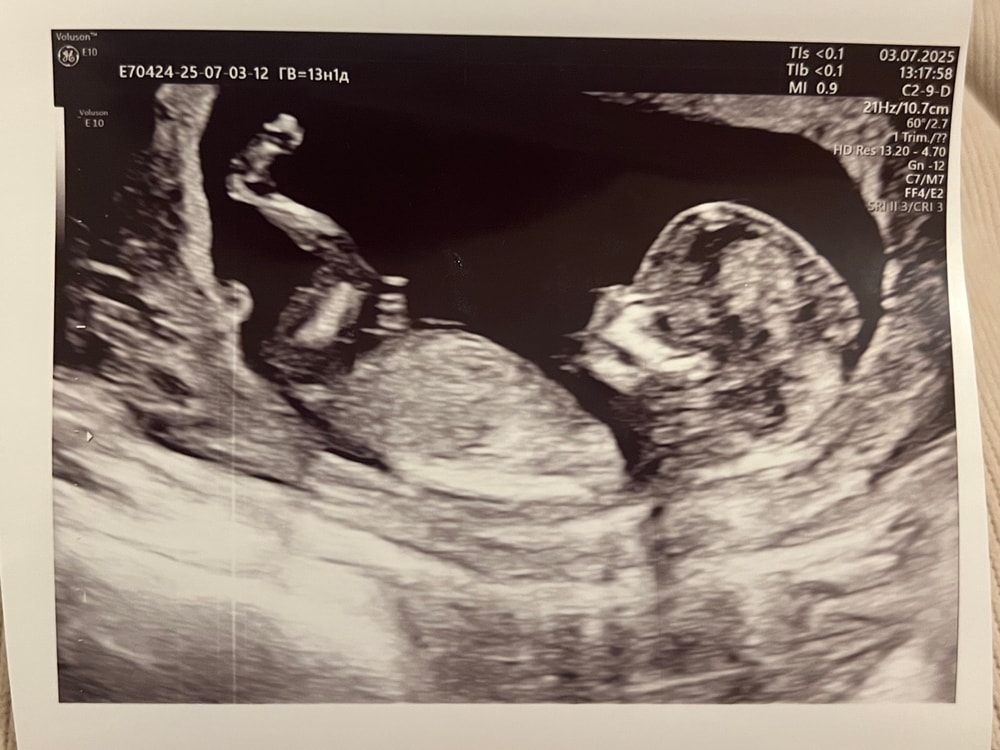

Не знаю кто там на снимке, но прикольно,когда детки целиком еще помещаются на экране) потом будете рассматривать только отдельные части и нифига не понятно будет)